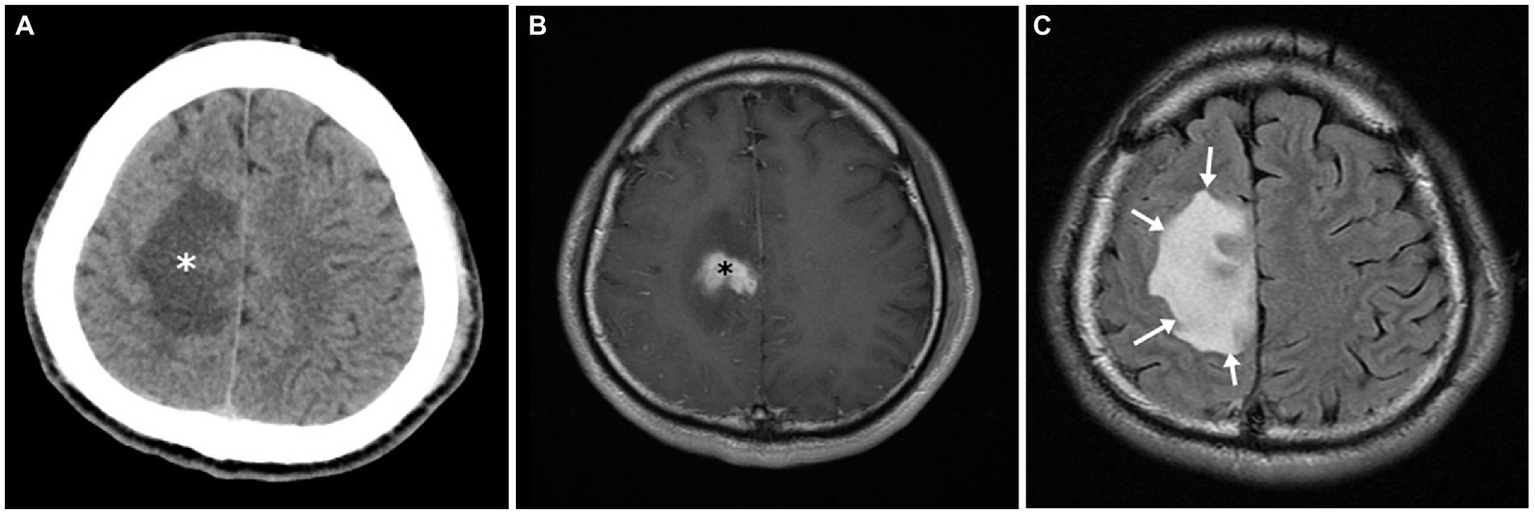

The typical radiological and radionuclide images of four melioidosis patients (case 1, 8, 2, and 9) are illustrated among Figures 1–3. The typical images from melioidosis patients are demonstrated in the computed tomography (CT) and magnetic resonance imaging (MRI) including low attenuated lesions with contrast enhancement surrounding the borders of lesion which abscess were diagnosed (Figure 1B, right mediastinal abscess; Figure 1C. splenic abscess with involvement of adjacent abdominal wall; Figure 2, brain abscess of right parietal lobe; Figure 3A. septic arthritis with abscess of the right knee joint). The radionuclide Tc-99 m MDP bone scan reveals increased radiotracer uptake in the corresponding right knee joint (Figure 3B).

Figure 2

Central nervous system melioidosis of case 2. Unenhanced computed tomography (CT) showed a low attenuation in right frontal lobe (white asterisk) (A). Magnetic resonance (MR) images of the corresponding region depicted hyperintensity in the T2 weighted fluid attenuated inversion recovery (FLAIR) sequence (white arrows) (B) and an enhancing soft tissue lesion in the post contrast T1 weighted images (black asterisk) (C). All image findings are compatible with encephalitis.

Salient but nonspecific findings such as focal consolidations in one or multiple lobes (especially upper lobes) and multiple small nodules and patches in radiographic images have been reported in nearly half of melioidosis patients with acute lung infection, which mimics the radiologic presentations of tuberculosis and atypical pneumonia (18). The visceral organ abscess of melioidosis displaying on computed tomography varies from micro- to large abscesses with characteristics of “honeycomb” or “Swiss cheese” appearance, from which other pyogenic abscess, Staphylococcus aureus infection, amebiasis, and tuberculosis should be differentiated (18). We have demonstrated four cases with visceral abscess (case 1, 2, 8, and 9) (Figures 1B,C, Figures 2, 3) and five cases with pneumonia (case 3, 6, 7, 10, 11) (Figure 1A; Table 1), which are comparable with previous literature (17, 18, 20).